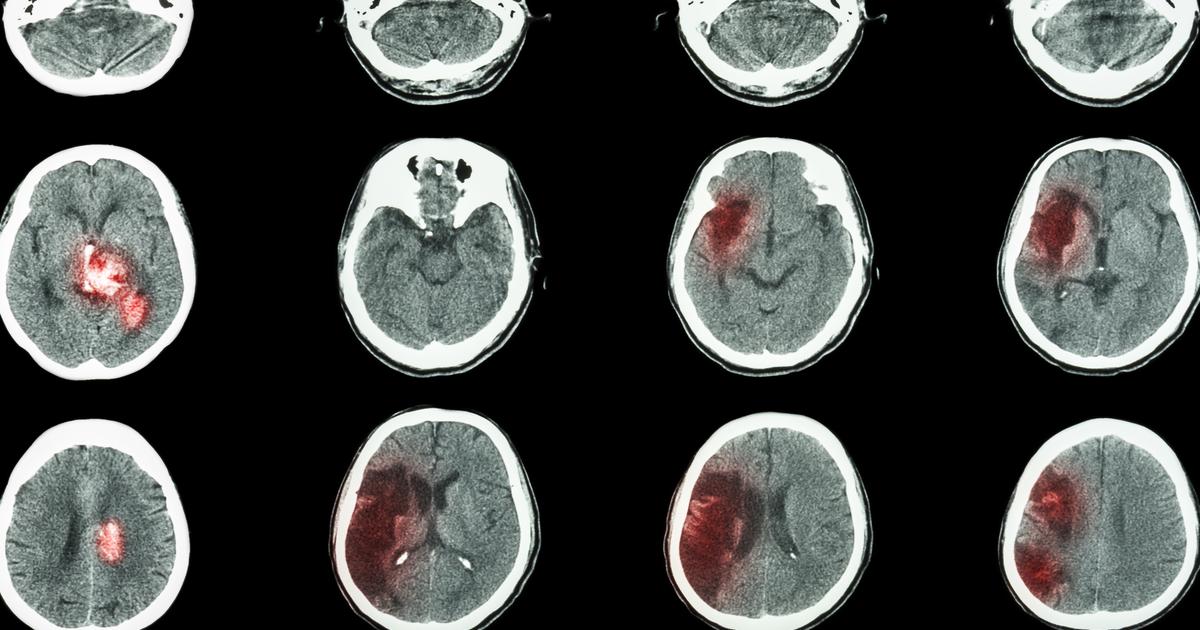

An infant or unborn child affected by an intraventricular hemorrhage may develop periventricular leukomalacia as a complication of their emergent medical event. Intraventricular hemorrhage is a term used to describe when an individual experiences a bleed inside or around their brain ventricles. Brain ventricles are the spaces in an individual's brain filled with cerebrospinal fluid. Periventricular leukomalacia occurs when the white matter in the spaces between the individual's ventricles becomes damaged and can no longer produce the protective myelin sheath that covers the nerves. An intraventricular hemorrhage causes blood to flow into these spaces that put excessive pressure on the cells that make up the white matter, which causes them to become damaged beyond repair and die. Intraventricular hemorrhage-precipitated periventricular leukomalacia is most common in babies born prematurely. The exact reason for this is not clear, but it is thought the increased fragility of a premature infant's blood vessels leads to their increased risk of intraventricular hemorrhage.